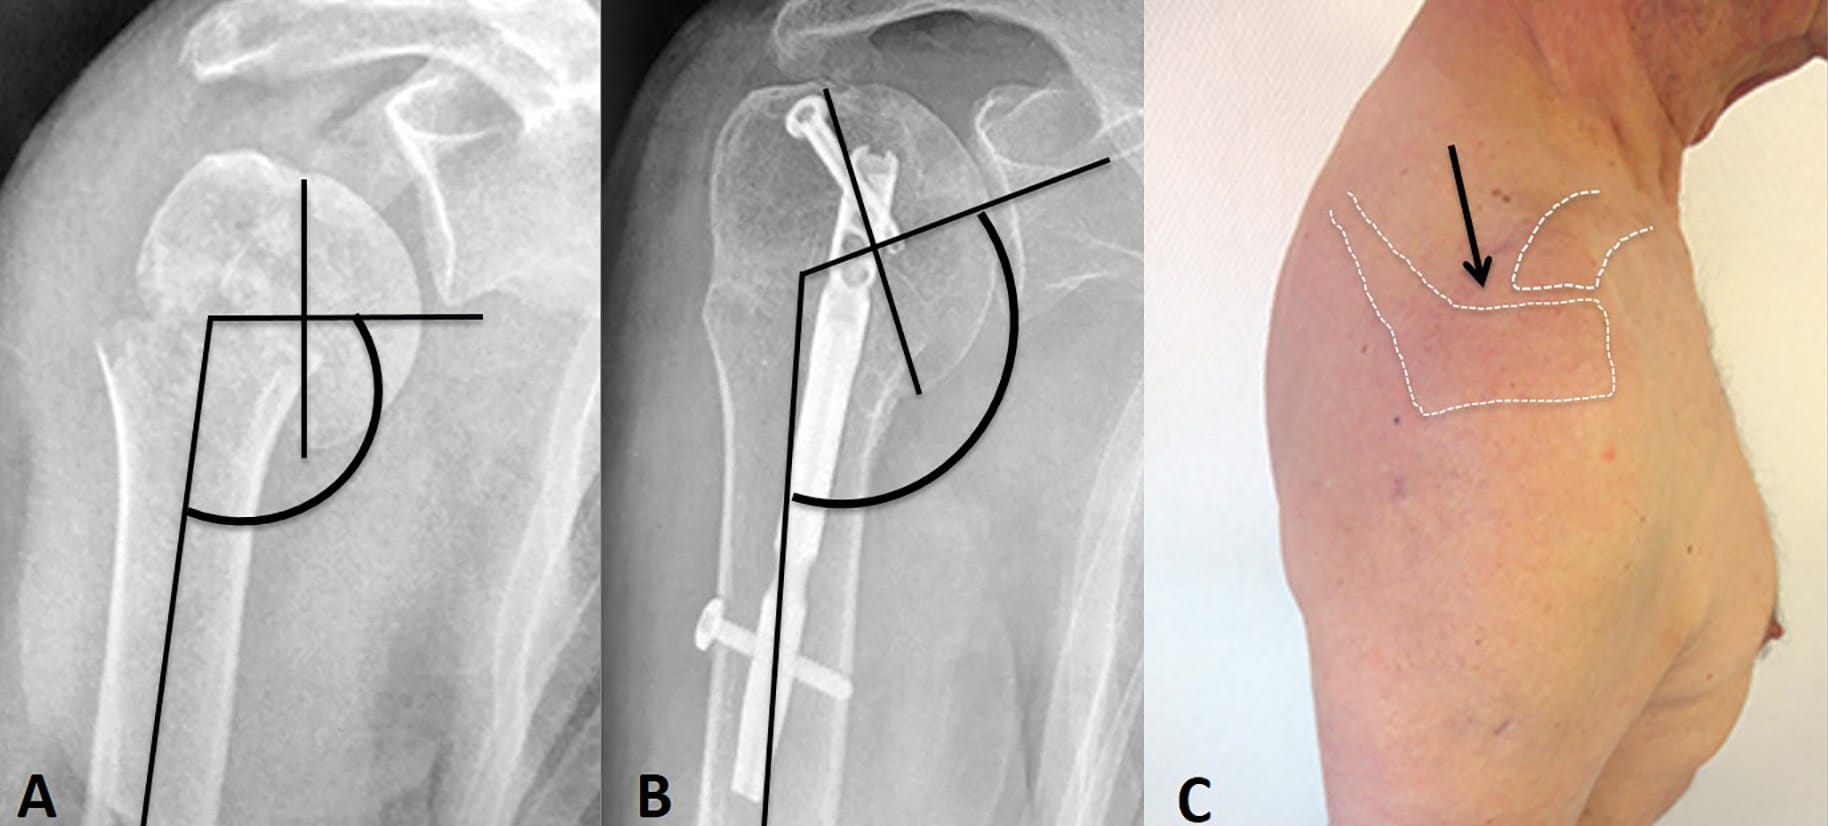

Using preoperative radiographs and CT-scans, surgical-neck fractures were classified in 3 types, according to the displacement of the humeral head fragment (Figure 6):

- Valgus Surgical-Neck Fractures (Type A- 8 cases): the medial translation of the diaphysis is partial and combined with some abduction which leads to valgus deformity of the humeral head.

- Translated Surgical-Neck Fractures (Type B- 19 cases): when the shaft is entirely translated medially and anteriorly by the pectoralis major and internally rotated by the latissimus dorsi and teres major, there is no more contact between the head fragment and the diaphysis, and therefore, no humeral head deformity.

- Varus Surgical-Neck Fractures (Type C- 14 cases): the shaft is translated laterally with some adduction, leading to varus head deformity.

With increasing surgical experience, we have used this classification to choose the optimal percutaneous entry point for the IM nail (Figure 7).

We observed one partial humeral head avascular necrosis ,as already mentioned, and two malunions, early in our experience: one patient had incomplete reduction of humeral translation whereas the other one developed a varus malunion of the surgical neck. Both fractures were noted to be mal-reduced at the time of surgery because of intraoperative technical error: the entry point of the nail was incorrect (i.e., too lateral). With increasing surgical experience, we developed a strategy to enter the nail at the correct spot, based on the type of displacement of the humeral head fragment (Figures 5, 6).

From a technical standpoint, optimal entry point for the nail is of paramount importance and must be based on the displacement of the humeral head fragment: the nail should enter more lateral in case of valgus tilt and more medial in case of varus tilt. The use of intraoperative fracture site impaction (“backslap” technique) reinforces the construct and allows immediate activity and rehabilitation.